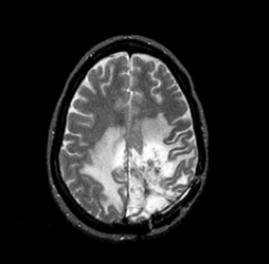

What can be seen in this scan?

[EXTRA? Possible MCQ]